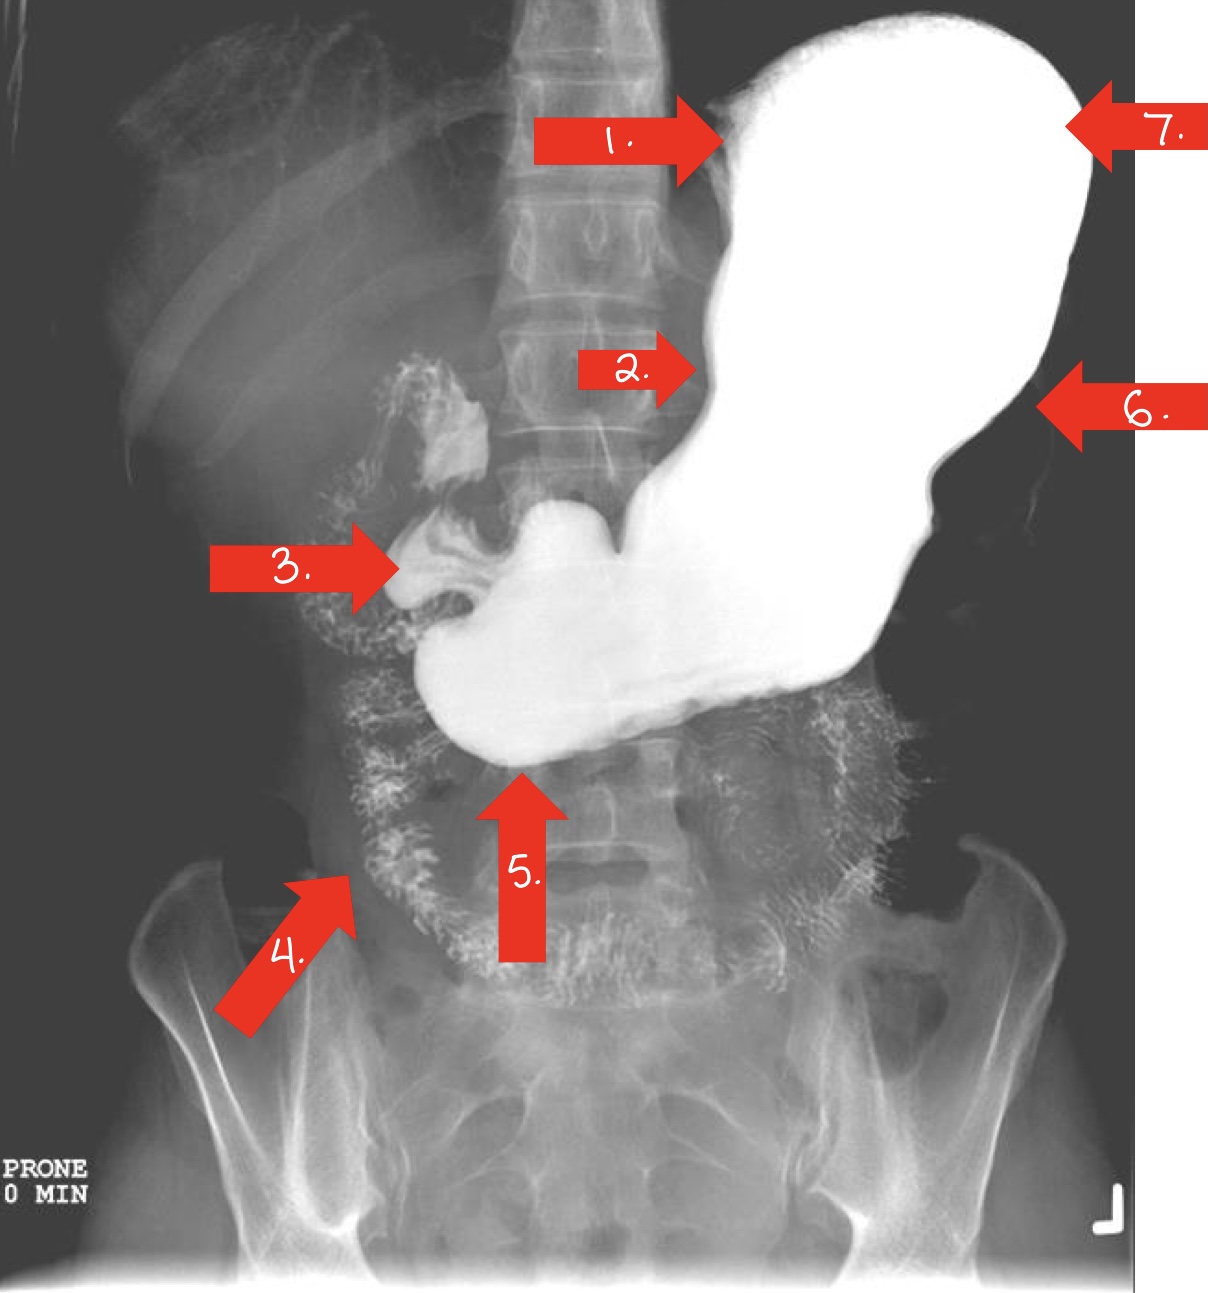

What is 1

gastroesophageal opening

lower esophageal sphincter

sometimes called cardiac antrum/sphincter

What is 2

lesser curvature/stomach

What is 3

doudenal bulb/small intestine

What is 4

jejunum/small intestine

What is 5

pylorus

or pyloric antrum

What is 6

greater curvature/stomach

What is 7

fundus/stomach

duodenal bulb/small intestine

ileum/small intestine